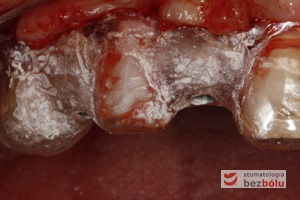

Pierwszy etap zabiegu implantologicznego - kształt cięcia błony śluzowej - przesunięty do podniebienia - zapewniający dostęp do kości

Pierwszy etap zabiegu implantologicznego – kształt cięcia błony śluzowej – przesunięty do podniebienia – zapewniający dostęp do kości